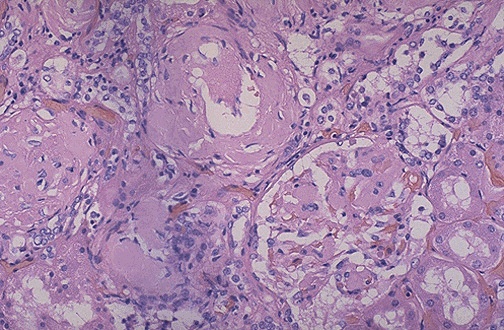

| The amorphous pink depositis of amyloid may be found in and around arteries, in interstitium, or in glomeruli, as seen here with H&E stain. A Congo red stain will demonstrate the pink material to be amyloid. Such collections of amyloid add to renal bulk, but diminish renal function. |